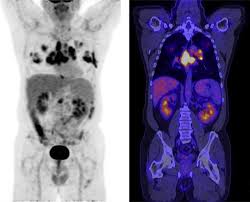

최첨단 현대의학으로 가장 적절한 방법이 양전자단층촬영술(Positron Emission Tomography, PET)이라고 나는 생각한다. PET는 체내 대사 변화를 촬영하는 기기로 CT나 MRI 다음에 개발된 영상장비이라고 한다.

요즘은 여기에 CT를 붙여서 PET 영상과 CT 영상을 융합해 서로 약점을 보완해 검사의 질을 더욱 높이고 있다고 한다.

여기에 방사성 핵종 F-18를 붙여(F-18 FDG라고 함) 혈관 주사하면 빨리 자리는 암세포는 포도당이 더 필요해 정상 세포보다 10∼100배 더 많이 모여들고 이를 방사능으로 촬영해 찾아낸다. 암이 1㎝만 돼도 10조개의 암세포가 있어 CT, MRI 소견이 애매한 경우 유용하게 쓰인다.

PET의 또 다른 장점으로 거의 모든 종류의 암을 찾아낼 수 있다는 것이라고 한다. 일반적으로 암세포는 포도당 대사가 높기 때문이라고 한다.

또 머리끝에서 발끝까지 촬영해 어느 곳에 있는 암이라도 잡아낸다. 다시 말하면 사각지대가 없다고나 할까? 이미 일본에서는 이 방법으로 암을 검진하는 프로젝트를 성황리에 진행하고 있다고 한다.